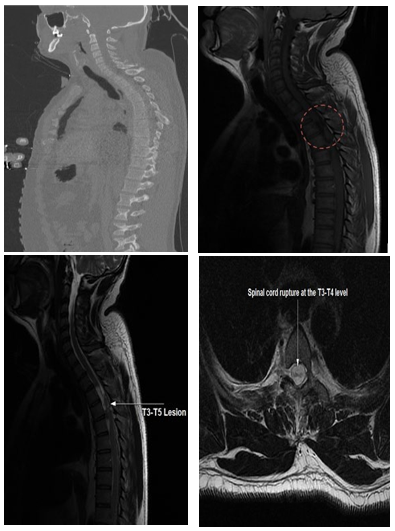

ACT scan of the spine shows no post-traumatic bony involvement (Figure 1 A). Spinal MRI shows a hypo signal T1 and T2 hyper signal lesion at the T3-T4-T5 level compatible with a complete section of the spinal cord (Figure 1 B-D).

Figure 1 :